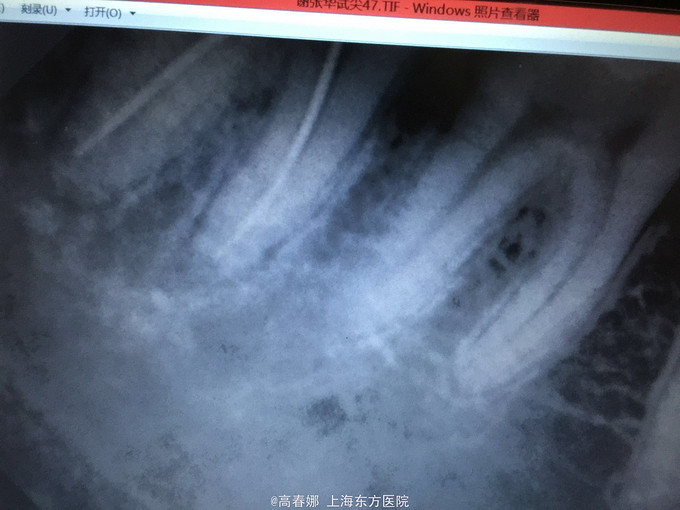

检查:47远中麟面龋坏,探诊(-),叩诊(+),松动I度,牙龈无明显红肿,牙周袋约3mm,冷诊(-)。 48近中阻生,未见明显龋坏,牙龈无红肿。 X线示:48近中阻生。47远中邻面龋坏及髓,根尖区低密度影像。

诊断:47慢性根尖周炎 48阻生齿(近中位) 治疗:48拔除后行47常规根管治疗后冠修复。

下颌智齿近中阻生导致第二磨牙和第三磨牙之间留有空隙,从而导致第二磨牙远中龋坏,很多患者都是以第二磨牙牙髓炎及根尖周炎情况就诊,临床上碰到类似病例,应及早建议病人预防性拔除此类阻生的智齿。